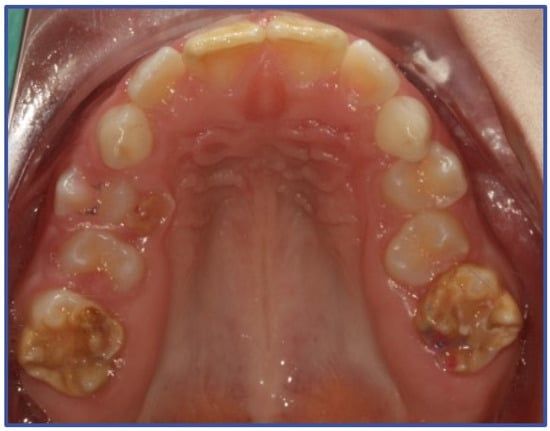

2. Materials and Methods

3. Results